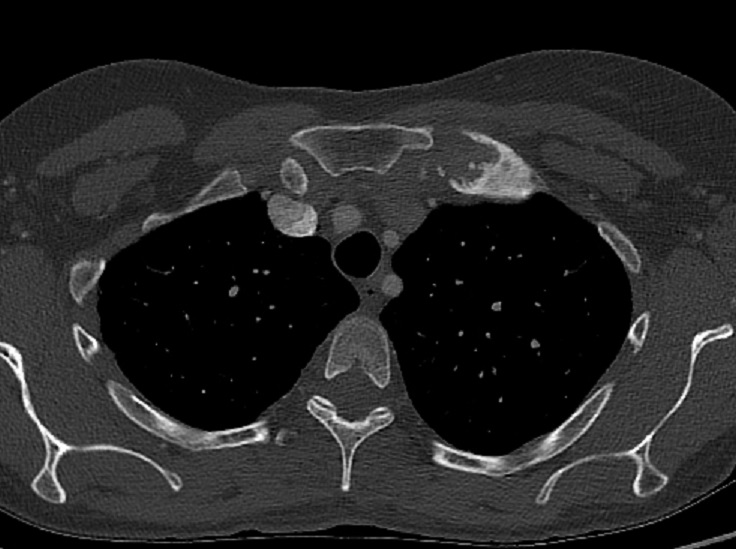

Aspect radiologique TDM du thorax fenetre

parenchymateuse d'une syndrome de SAPHO avec lesion

de osteite tumefiee de articulation

sternoclaviculaire droit et gauche . Image de

hyperdense de osteoscerose hyperostose metaphysaire

du têtes de clavicule droit et gauche être en vue |